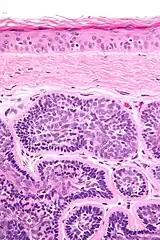

| Micrograph of a dermal cylindroma. H&E stain. | |

- Dermal lesions consisting of nests of cells that are surrounded by hyaline (i.e., glassy, eosinophilic, acellular) material and have:

- Hyperchromatic nuclei that may palisade (columnar nuclei arranged around the periphery of the cell nests with their short axis tangential to the nest periphery), and

- Cells with lighter staining ovoid nuclei at their centre.

They lack of a significant number of lymphocytes; this differentiates them from spiradenomas.